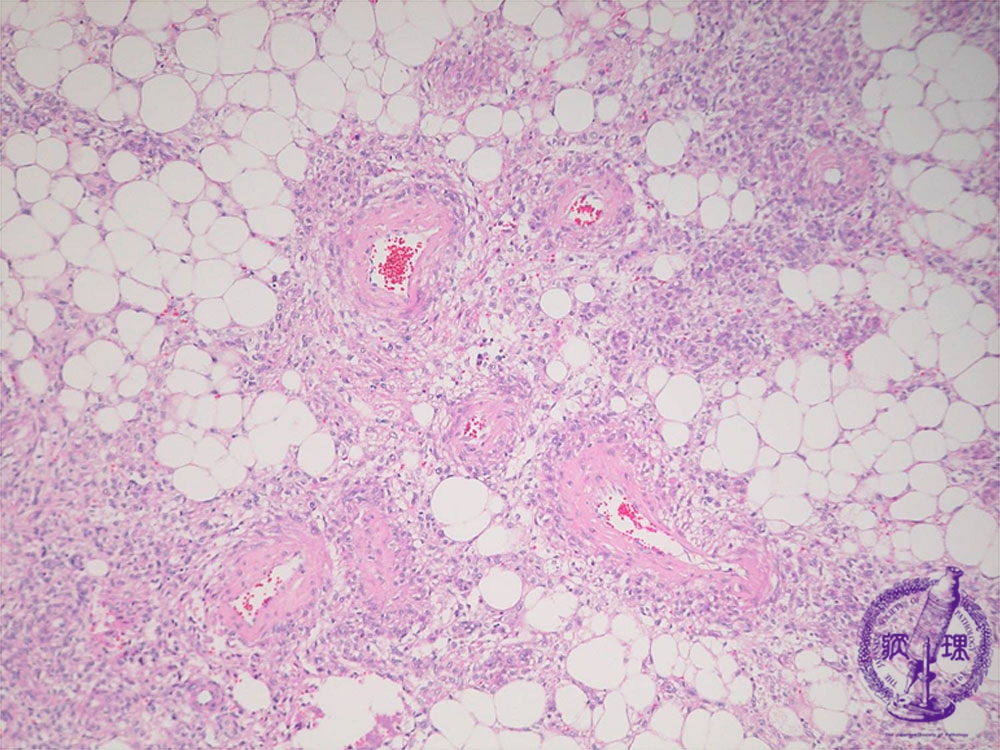

- (18)Angiomyolipoma(Tuberous sclerosis)

Microscopic findings ( HE, middle power view): The tumor contains adipose tissue, thick-walled blood vessels and smooth muscle-like spindle cells.